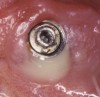

Radiographically, in peri-implantitis, vertical destruction of the crestal bone is present around the implant—which assumes the shape of a saucer—while the bottom part of the implant remains osseointegrated. In some instances, wedge-shaped defects develop along the implant (Figure 1). In addition, there is a peri-implant pocket and bleeding after gentle probing with a blunt instrument, and there may be suppuration from the pocket (Figure 2 and Figure 3). Tissues may or may not be swollen; however, hyperplasia is frequently seen if implants are located in an area with non-keratinized mucosa or if the suprastructure is an overdenture. Pain is not present.9 Both a mean loss of peri-implant bone height amounting to 1 mm to 1.5 mm in the first postsurgical year and vertical bone loss of less than 0.2 mm annually following the implant’s first year of service have been proposed as major criteria for success.18-20 It should be noted that peri-implant bone loss also occurs in cases of overload and faulty occlusion and may be be related to the type of implant used. The implants with the longest smooth surfaces demonstrated the highest amounts of bone resorption 12 months after abutment connection.21 Mobility of an implant suggests complete bone loss and, therefore, complete failure. To prevent this, peri-implant disease should be recognized earlier, to allow intervention before a substantial portion of the supporting bone is lost. However, mobility in early periods of osseointegration is not a very reliable clinical indicator of peri-implantitis. Therefore, electronic measuring devices should be used.

Figure 2